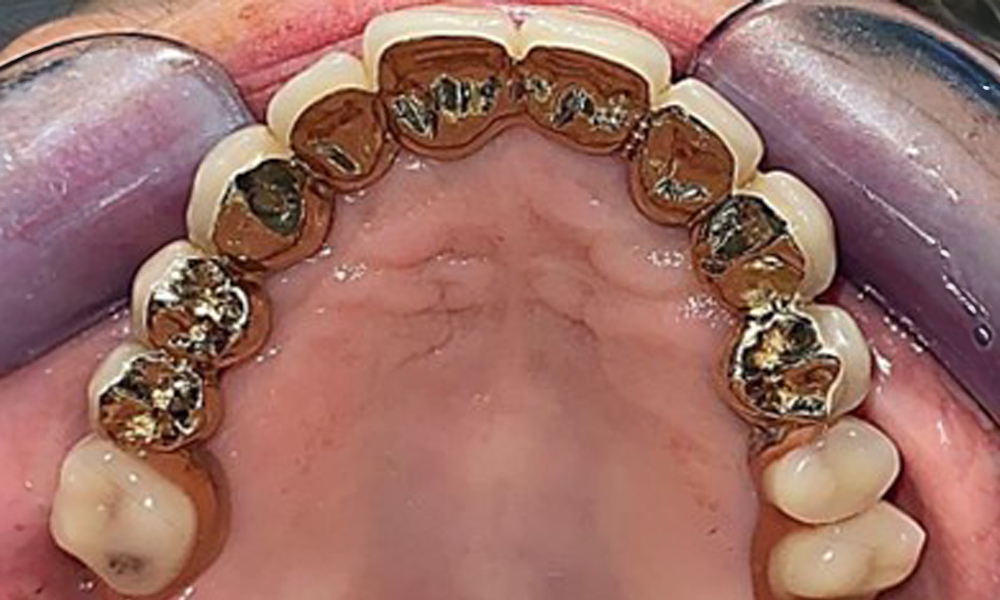

The patient was fitted with a combined removable maxillary telescopic prosthesis more than 25 years ago (Fig. 1, Fig. 2, Fig. 3) and is very happy with her dentures. The patient has an adequate fixed denture for the mandible (Fig. 4).

The dental findings are as follows: Combined removable implant and tooth-supported telescopic prostheses on implants 15, 13, 21, 23, 24, 25 and tooth 11 (Fig. 1, Fig. 2, Fig. 3). The patient was fitted with a fixed mandibular denture. Adequate bridges were present over 37 to 34 and 45 to 47 (Fig. 4), the crown margins were intact and there were no active caries. A composite filling with a marginal gap was present on tooth 43. There was mandibular gingival recession, exposing 1 to 3 mm of root surface. This also applies to 11.

Occlusal view: Maxilla with removable, palateless denture.

Fig. 3: Occlusal view: Maxilla with removable, palateless denture.